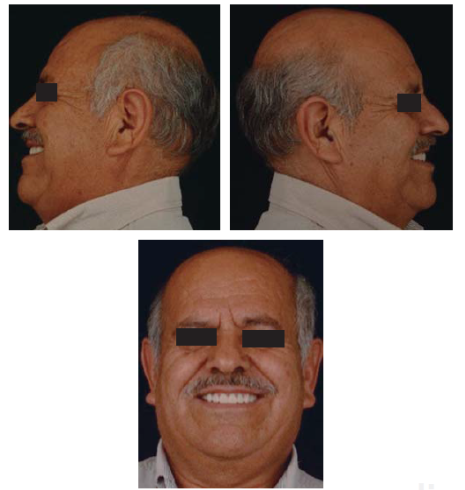

Se controló al paciente por espacio de un mes y medio para verificar su fase de adaptabilidad al tratamiento y su condición fue satisfactoriamente estable, cómoda y sobre todo funcional (Figuras 42a45).